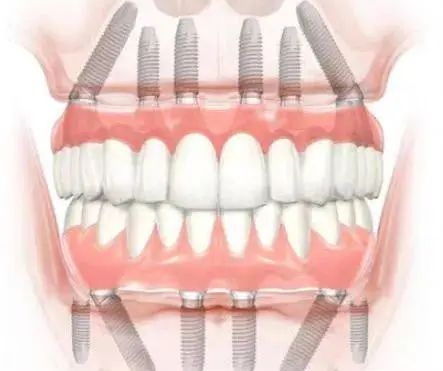

4. 于都美康口腔:专注疑难种植,骨条件差也能种

为什么推荐:专门做复杂种植,比如骨量不足、全口无牙的患者。医生经验比较丰富,成功概率高。

真实实例:我表姐骨量少,跑了3家诊所都说不能种,之后在美康口腔种成功了!

江西于都哪个店种植牙好优势:疑难种植医生、成功概率高、方案个性化

价格参考:种植牙4500元起(美国皓圣)